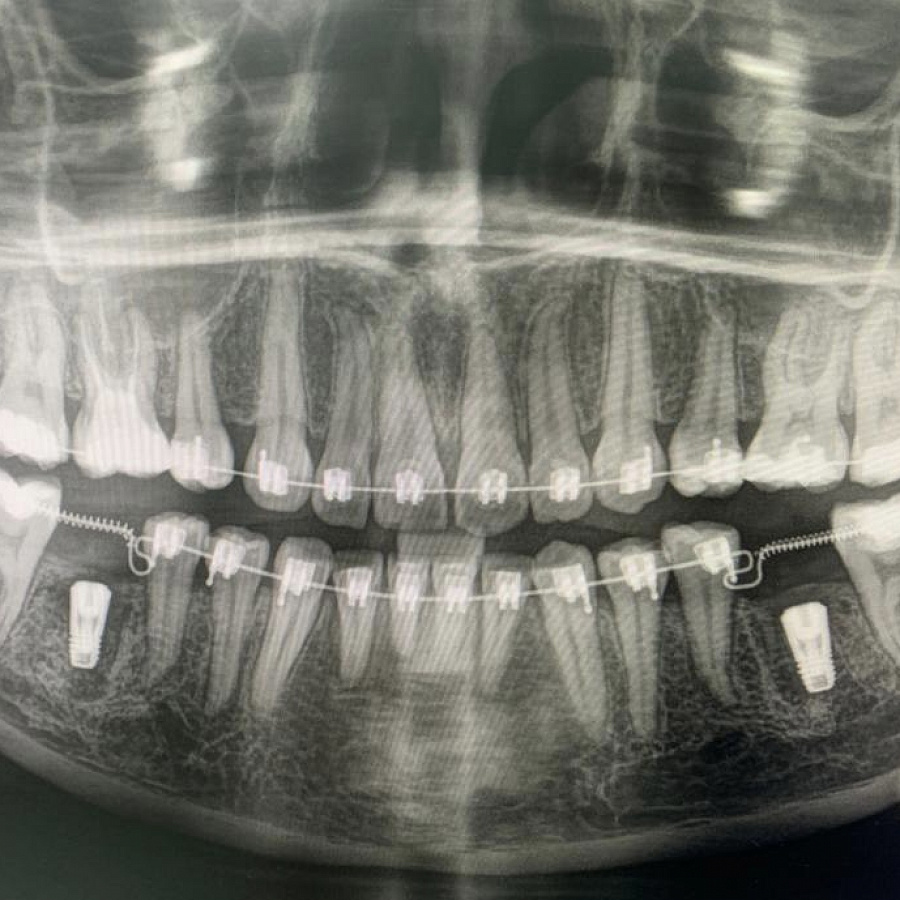

В ходе диагностики мы выяснили, что нижние шестерки вылечить невозможно. В таком случае необходимо удалить зубы и установить имплантаты.

Пациентка начала ортодонтическое лечение и за 5 месяцев до окончания лечения ей удалили нижние шестерки и поставили импланты. За месяц до конца лечения установили формирователи десны. На момент снятия брекетов были сняты слепки под постоянные коронки на имплантатах.

В этом случае одновременно пациент закончил ортодонтическое, хирургическое и ортопедическое лечение. Что возможно только при одновременном подходе команды врачей.